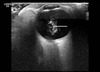

Desprendimiento de retina

Retinopatía vítrea proliferativa

Desprendimiento de retina exudativo inducido por melanoma

Hemorragia supracoroidea

Desprendimiento de coroides

Desprendimiento de retina y coroides